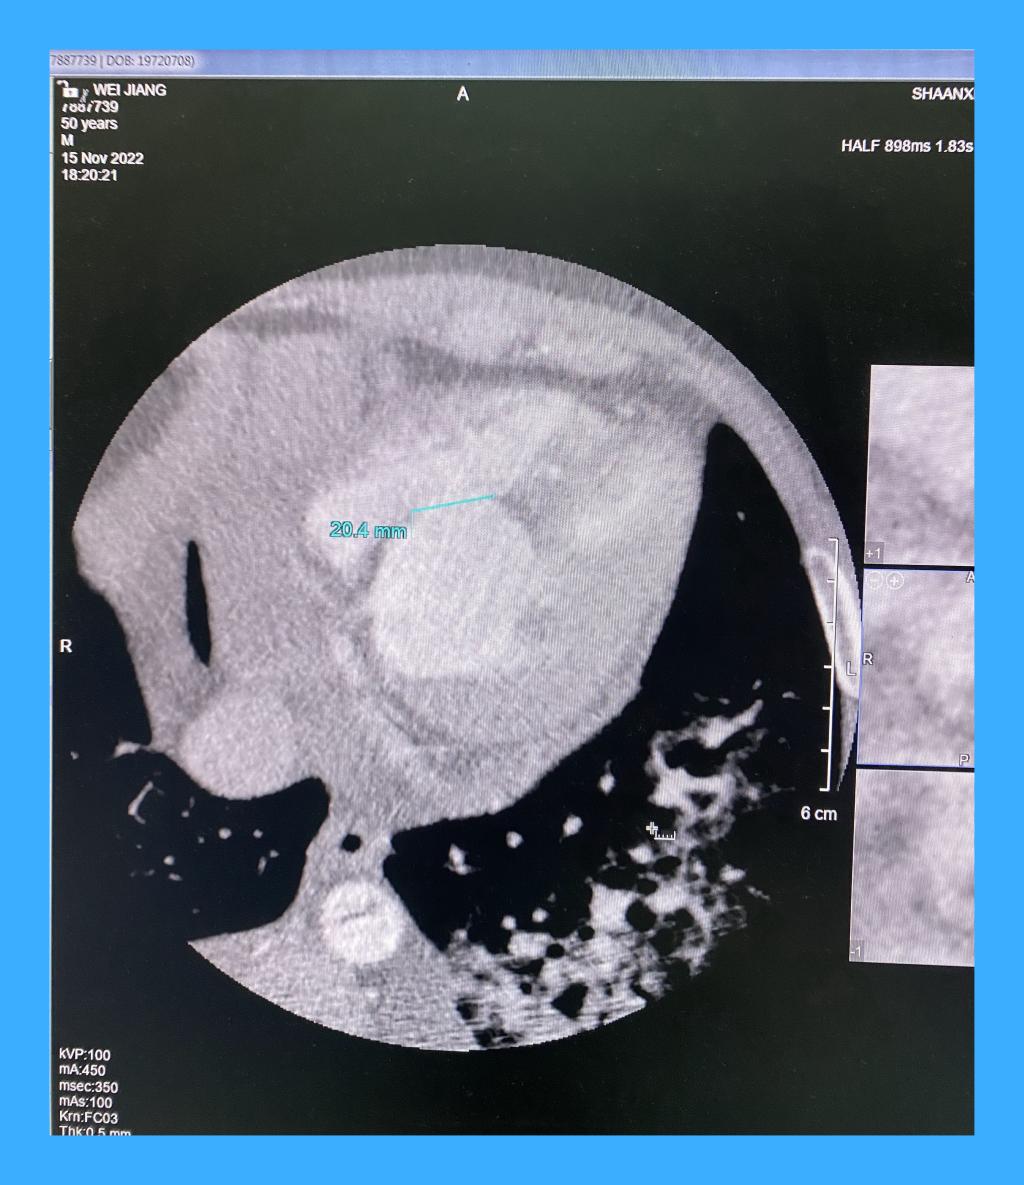

专家立即与黑料网心脏内科梁磊主任联系后,立即将患者转入黑料网心脏外科,付建莉主任医师心脏超声检查,确诊为心脏左室下壁瘤样膨出,与正常室壁呈矛盾运动,测其瘤口为41mm,瘤深27mm,后室间隔下壁回声失落,左室面缺损口大小38mm,右室面缺损口大小21mm,病情十分危急。

心包切开后,发现大量血性心包积液,室壁瘤已经发生破裂,心脏严重水肿,经室壁瘤切口探查,发现一个近30毫米的巨大室间隔穿孔。术后经食道超声证实,室间隔穿孔消失,左心室前侧壁和下壁活动度改善,瓣膜未见反流。手术顺利结束,患者安全回到心外科ICU。